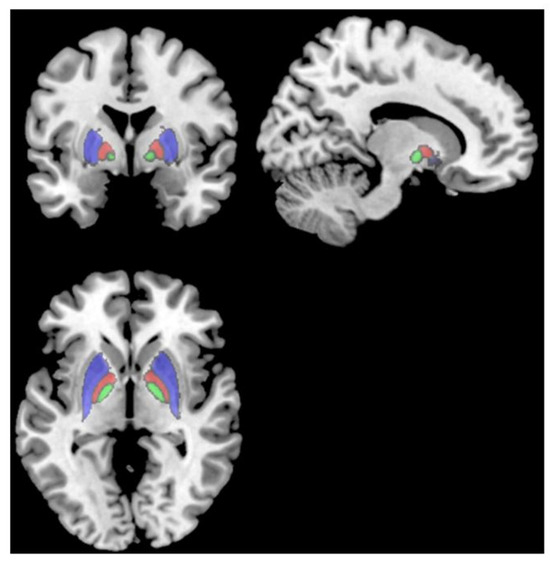

Lastly, Deters et al. [23] explored brain volume and glucose metabolism changes in 33 people with prior mild COVID-19, divided into a <6-month post-infection group (n = 18) and a >6-month post-infection group (n = 15). The >6-month group showed smaller volumes in the putamen, pallidum, and thalamus compared to the <6-month group. Fatigued subjects in the >6-month group also had smaller frontal lobe volumes than non-fatigued subjects. Worse fatigue severity and perceived fatigability were associated with smaller frontal lobe volumes in the >6-month group. There were no differences in brain glucose metabolism between the <6-month and >6-month groups. However, both groups showed hypo- and hypermetabolism in certain regions compared to a healthy normative database. The results suggest that mild COVID-19 may lead to delayed decreases in subcortical and frontal lobe volumes, particularly in those with persistent fatigue (Figure 2; [23]). The mechanisms are unclear but could involve basal ganglia–cortical circuits underlying motivation and motor control.

Figure 2.

T1 MRI showing the putamen (red), pallidum (cyan), and thalamus (green), which all had smaller volumes in subjects > 6 months post-infection than subjects < 6 months post-infection [23].